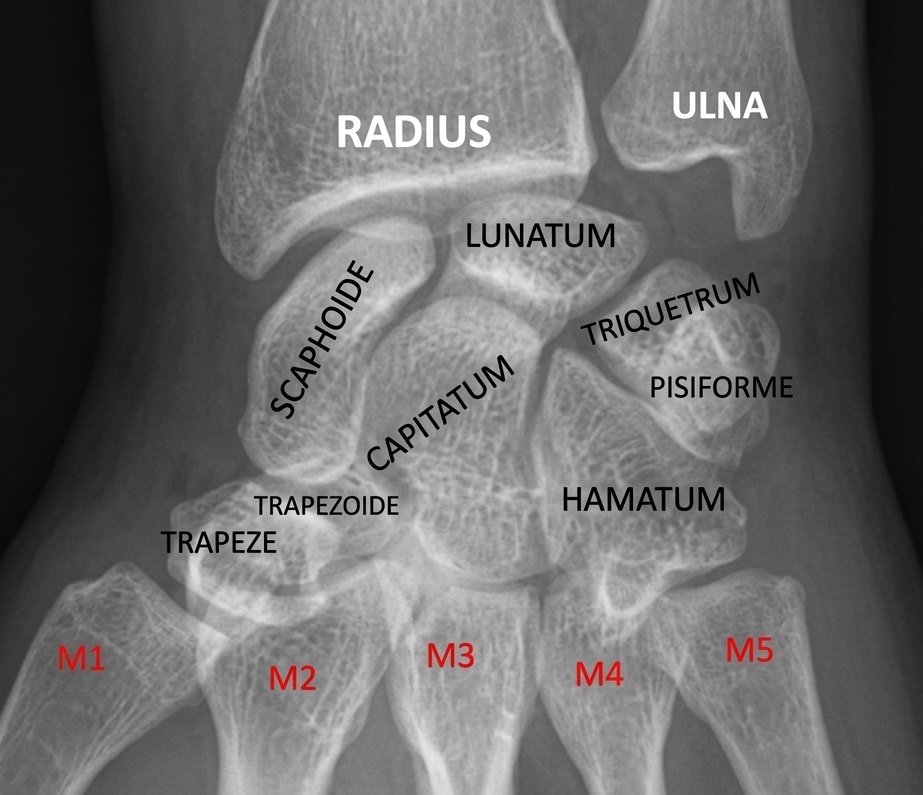

Bon alignement des structures osseuses et respect des rapports anatomiques.

Absence de lésion osseuse décelable, notamment post-traumatique.

Pas de signe d'épanchement articulaire.

Parties molles sans particularité.

Respect des interlignes articulaires du carpe et des phalanges.

Pas d'érosion osseuse ni de lésion suspecte.

Pas de lésion post-traumatique récente.